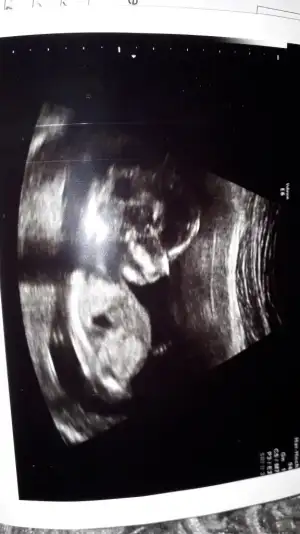

Kız gibi birde 11 yada 12 hafta usg paylaşırmısınızTeyzeleri bizde tahmin bekliyoruz 13+6 gunlukbizim grupta da tahmin edenler oldu bakalim siz ne diyeceksiniz

10+0 haftalik başka yok yani 11 yada 12 yokKız gibi birde 11 yada 12 hafta usg paylaşırmısınız

Ay hadi bakalimKız gibi birde 11 yada 12 hafta usg paylaşırmısınız

10 hafta nub iki tarafa benzer ama sanki kız yönünde gibi 16+ haftadasınız ogrenmedinizmi10+0 haftalik başka yok yani 11 yada 12 yok![]()